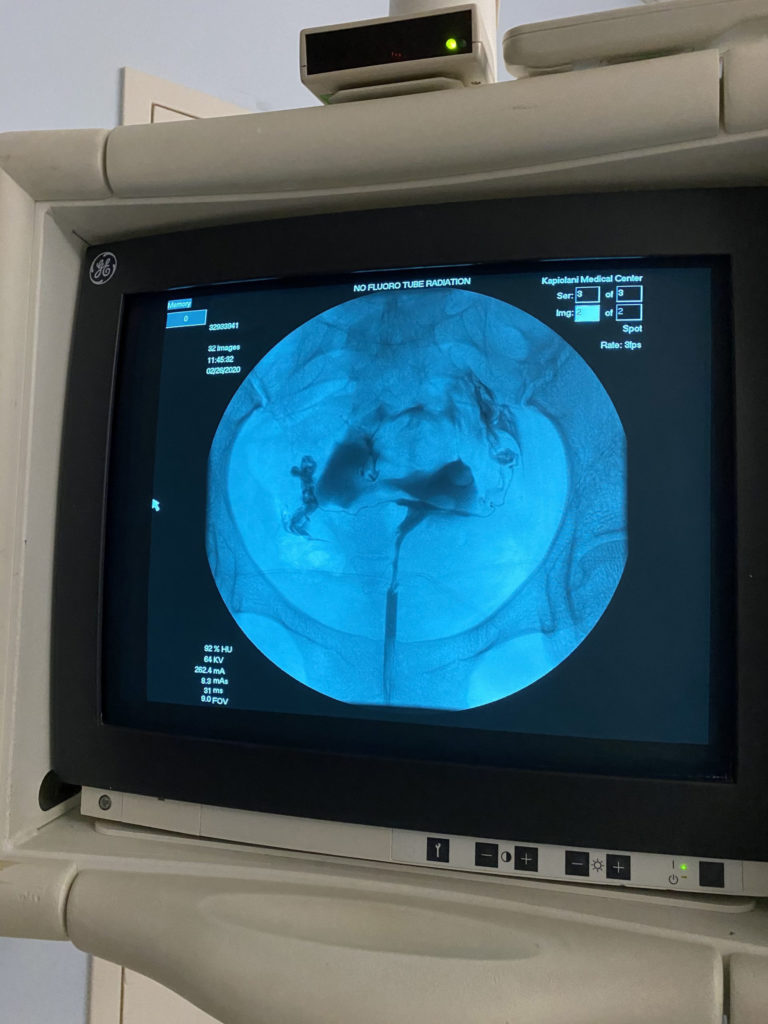

She removed the speculum and the nurse and student dragged the sheet under me so I slid up on the table and was positioned under the fluoroscopy camera. My RE waited for the Radiologist to be ready before she blew up the tiny ballon at the end of the catheter to the size of a pea. That sounds tiny, but it felt huge inside of me. Then she filled my uterine cavity, fallopian tubes and peritoneal cavity with dye from the catheter. When the dye was filling my fallopian tubes it felt like EXTREMELY bad cramps, but only for one minute. Once it was over it felt like normal period cramping. When the dye was going through my fallopian tubes, the Radiologist was taking the fluoroscopic images.

It was also good to have my RE do it because she saw the results instantaneously. She said my left fallopian tube was totally clear because the dye spilled out quickly. She wasn’t sure about my right tube so I had to roll all the way over and back onto my back to move the dye around and get more images taken, then she saw that my right tube was open too.